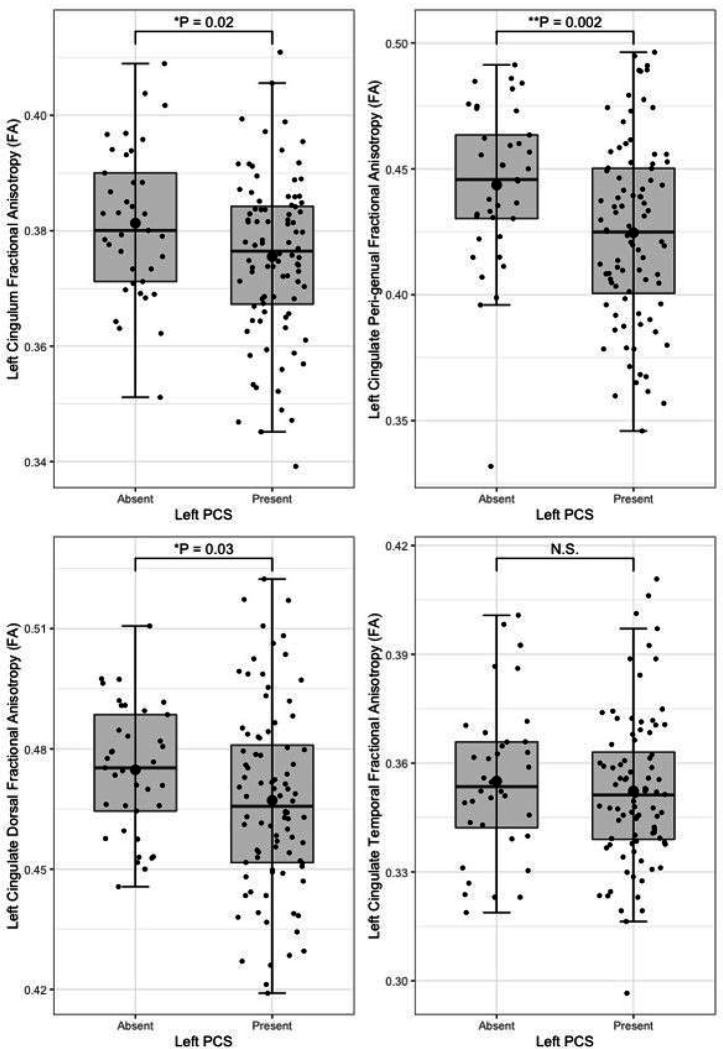

Presence of a left paracingulate sulcus was associated with reduced fractional anisotropy in the left cingulum (P = 0.02) bundle and the peri-genual (P = 0.002) and dorsal (P = 0.03) but not the temporal cingulum bundle segments. Left paracingulate sulcal presence was associated with increased left peri-genual radial diffusivity (P = 0.003) and tract volume (P = 0.012). A significant, predominantly intraregional frontal component of altered resting state functional connectivity was identified in individuals possessing a left PCS (P = 0.01). Seed-based functional connectivity in pre-defined networks was not associated with paracingulate sulcal presence.

Following quality control procedures segmentations were available for 125 subjects, (mean age 52.19, SD 5.12), see Table 1. The frequency of present to absent PCS was greater in the left (88/125) than right (71/125) hemisphere as expected. Individuals with a present left PCS displayed reduced FA of the left CG relative to individuals with an absent left PCS (β = −0.02, CI −0.01 – −0.0008 μm2/ms, P = 0.02). Using the Xtract method a present left PCS was associated with decreased FA in the ipsilateral CBG (β = −0.009, CI −0.04 – −0.008 μm2/ms, P = 0.002) and CBD (β = − 0.009, CI − 0.02 – − 0.0009 μm2/ms, P = 0.03) but not the CBT. These results are displayed in Fig. 5. Ipsilateral RD of the CBG was higher in individuals with a present left PCS compared to those with an absent left PCS (β = 2.22 ×10− 5, CI 7.58e-06-3.69e-05 μm2/ms, P = 0.003), see Fig. 6. Ipsilateral RD was similar according to PCS presence in the other studied tracts in both hemispheres.

Results from the tract segmentation analyses indicate that absence of a left hemisphere PCS is associated with higher ipsilateral cingulate bundle FA. More specifically group diffusivity differences localise to the anterior portion of the cingulum; the peri-genual and dorsal cingulum bundles. Expectedly, no significant group diffusivity difference was observed in the offsite temporal division of the cingulate bundle. Furthermore, higher radial diffusivity and tract volume were observed in the left peri-genual cingulum bundle in individuals with a left PCS relative to those without. Ipsilateral tract volumes and diffusivity matrices were similar in the SLF-I between groups in both hemispheres. These results suggest that where a left PCS is present the ipsilateral cingulum bundle, specifically its anterior portions (peri-genual > dorsal) may display increased orientational dispersion. To the best of our knowledge these findings are novel and an association between gyrification and structural connectivity in healthy individuals has not previously been identified in the literature.